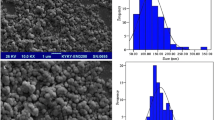

Molecular dynamics (MD) simulations of chitosan (CS) and albendazole (ABZ) were performed in the presence (BW1 BW2 and BW3) and absence (B1, B2 and B3) of water to evaluate CS/ABZ interactions in synthesis and solubility through solvation effect of nanoencapsulated ABZ. Molecular chemical reactivity was investigated through DFT-based reactivity descriptors, electrophilicity (ɷ), chemical potential (μ) and chemical hardness (η) as well as values of boundary molecular orbitals HOMO and LUMO that revealed interactions of the amino and hydroxyl groups of CS with groups of nitrogen, sulfur and ABZ ester bond. MD showed BW1 and BW2 with best Radial Distribution (RDF) profiles in aqueous medium as well as solvation energy indicating spontaneous formation of BW1 and BW2 nanoparticles. MD simulations demonstrate CS as a carrier capable of spontaneously encapsulating hydrophobic ABZ molecules in water-containing environments. Thus, a new perspective was presented for planning and design of controlled drug delivery systems with low solubility through MD.